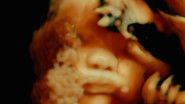

De humani corporis fabrica

Titolo originale: De humani corporis fabrica

Generi: Documentario